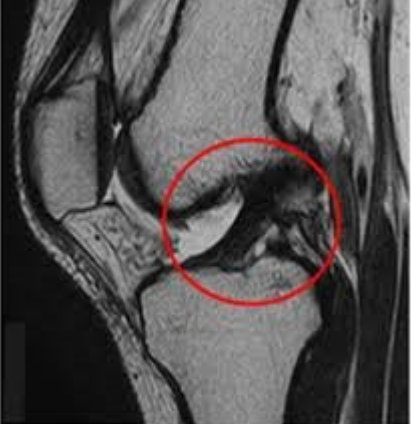

そして、関節の検査では、靭帯や軟骨といった柔らかい組織を調べることができます。レントゲンでは主に骨の評価が中心となりますが、MRIでは関節の中の状態まで確認できるのが大きな強みです。

関節(膝・肩など)